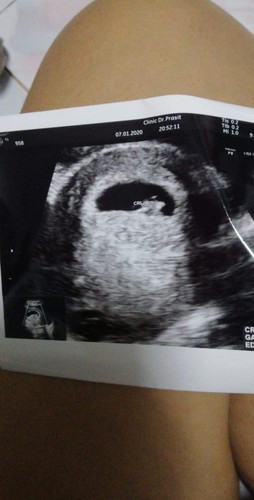

ลักษณะแบบนี้ปกติไหมค่ะ หมอบอกว่า เด็กตัวเล็กกว่าถุงน้ำ แต่เราจำวันเลือดขาดไม่ได้ค่ะ